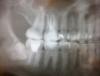

gidra002 Опубликовано 7 февраля, 2013 Поделиться Опубликовано 7 февраля, 2013 Здравствуйте, уважаемые стоматологи! Меня зовут Наталья и мне 21 год. На днях очередной раз посетила стоматолога. У меня депульпирован 3,5 года назад 6-й зуб на верхней челюсти справа, фотополимерная пломба тогда же была сделана. Недавно сделали ОПТГ, пролечили вторичный кариес на этом зубе, и стоматолог сказала, что на него надо ставить коронку, иначе возможны сколы и трещины в области корней.Скажите пожалуйста, так ли необходима коронка? Второй день успокоиться не могу, всё думаю об этом, чуть ли не реву, мне всего 21, были брекеты с 11 до 16 лет на обеих челюстях - мучение одно, а теперь это... Коронка и стоит не дешево, и зуб обтачивать в не малом объеме. Если и ставить, то какой вид? Металлическую я не хочу, потому что улыбнусь - и заметно будет.Снимки прикладываю к сообщению.Спасибо вам за внимание. Ссылка на комментарий

Magdalena Опубликовано 7 февраля, 2013 Поделиться Опубликовано 7 февраля, 2013 Коронка - надежный метод сохранить зуб. Пломба действительно обширная, своих тканей зуба мало, коронка защитит зуб от сколов при жевательной нагрузке, которую зуб на себе испытывает.Современные коронки - металлокерамические и безметалловые (диоксид циркония или алюминия), в интернете много информации, последний вариант - это высокоэстетичные и высокоточные коронки. Только сначала рекомендую сделать прицельный снимок зуба, чтобы убедиться. что корни хорошо пролечены (по панорамному снимку "размыто" видно).Обратите также внимание на 7 нижний справа, он тоже депульпирован, возможно его тоже лучше восстановить коронкой или керамической вкладкой, но сначала прицельный снимок, а то совсем не видно, как корневые каналы запломбированы. Ссылка на комментарий